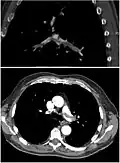

Ventilation/perfusion scan

Ventilation-perfusion scintigraphy

(A) After inhalation of 20 mCi of Xenon-133 gas, scintigraphic images were obtained in the posterior projection, showing uniform ventilation to lungs.

(B) After intravenous injection of 4 mCi of Technetium-99m-labeled albumin, scintigraphic images are shown here in the posterior projection. This and other views showed decreased activity in multiple regions.

A ventilation/perfusion scan (or V/Q scan or lung scintigraphy) shows that some areas of the lung are being ventilated but not perfused with blood (due to obstruction by a clot).[19] This type of examination is as accurate as multislice CT, but is less used, due to the greater availability of CT technology. It is particularly useful in people who have an allergy to iodinated contrast, impaired kidney function, or are pregnant (due to its lower radiation exposure as compared to CT).[66][67][68] The test can be performed with planar two-dimensional imaging, or single-photon emission computed tomography (SPECT) which enables three-dimensional imaging.[59] Hybrid devices combining SPECT and CT (SPECT/CT) further enable anatomic characterization of any abnormality.[69]